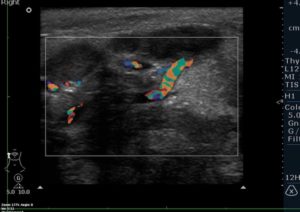

Важны и оборудование, и врач. Некомпетентный врач даже за самым навороченным аппаратом может принять за норму то, что нормой не является. Например, при осмотре сосудов есть дополнительные отражения. Это не патология, но неквалифицированный врач может принять их за тромб. В этом случае врачу бы помог опыт.